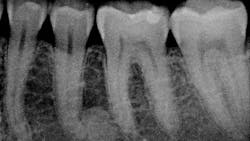

Patient: 41-year-old female

- Large, radiopaque mass just distal to apical third of no. 20

- Area not tender to palpation

- Tooth tests vital and WNL

- Normal health history